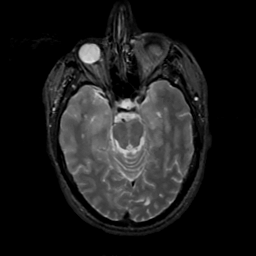

MR Study #6, March 17, 1991 -- Slice #18

[Home][Help][Clinical][Tour 1][Tour 2] Slice 18